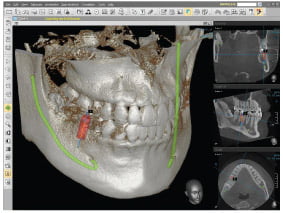

Our C.T. scanner is the E Woo Picasso scanner, used for 3D imaging of the jaws.

CT scans are 3 dimensional images of your bone – We are very proud to be only one of a few practices in Berkshire to have a CT scanner in house.

Our Preferred CT Scanner is the E-Woo Picasso from Vatech & E-woo Technology, used for 3D imaging of the jaws.

Being the world’s best selling 3 in 1, Picasso trio scanners have been installed in about 2,000 sites around the world. It offers all anatomical information like septum, cyst, etc in the sinus in cases like multi or full mouth implant surgery, at once.

Below are some screen images of the information we gain that is invaluable to the dental Implant process as it allows to visualise the placement in 3D. The main benefit is that as we know the anatomy of the site where the implant is placed we do not have to make large cuts(incisions) in the gum. Implants are placed through a very small hole in the gum therefore reducing healing time and post surgery discomfort and swelling.